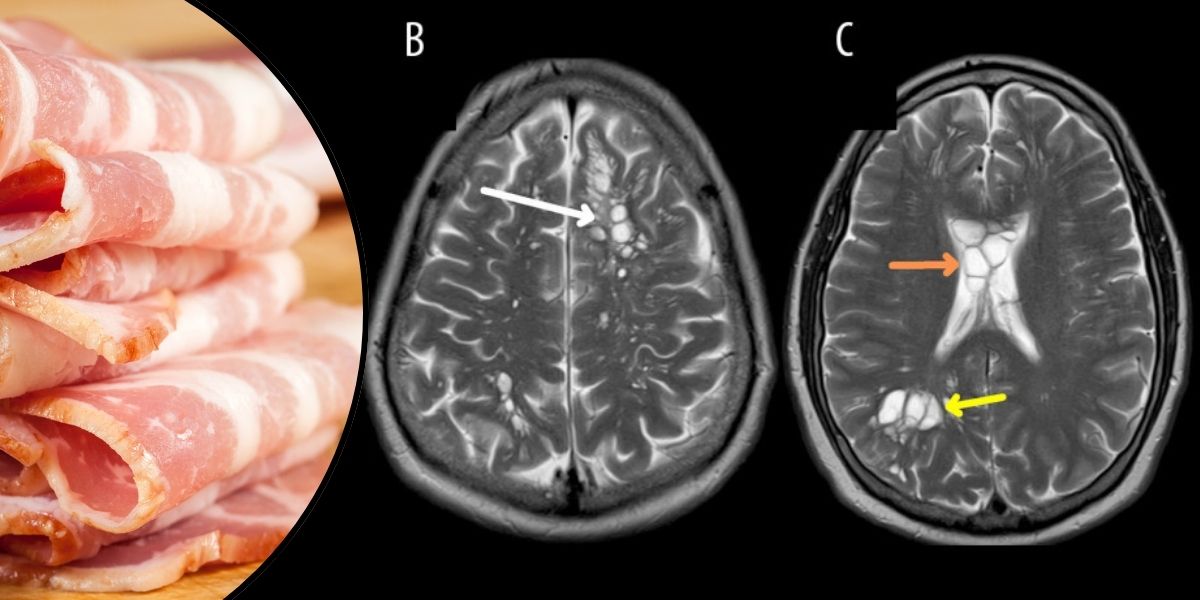

52 yaşındaki adam, ilaca yanıt vermeyen şiddetli migren ağrıları için tıbbi yardım istedi. Bilgisayarlı tomografi taraması yaparken doktorlar şok edici bir keşifte bulundu: beyninde sistiserkoz olarak bilinen bir duruma yol açabilen çok sayıda tenya larvası kisti vardı.

İlginç bir gelişme mi? Adamın az pişmiş, pek de çıtır olmayan domuz pastırmasını yeme konusunda uzun süredir devam eden bir alışkanlığı vardı. Doktorlar bu yeme alışkanlığının rol oynayabileceğini öne sürerken, aynı zamanda bu tür enfeksiyonları önlemek için ellerin doğru yıkanmasının önemini de vurguladılar.

American Journal of Case Reports'ta yayınlanan rapor, az pişmiş domuz pastırması tüketimiyle ilişkili potansiyel sağlık risklerinin altını çiziyor. Tenyaların pastırmadan mı yoksa yetersiz el hijyeninden mi kaynaklandığı hala belirsiz olsa da, tavsiyemiz pastırmanızın çıtır olduğundan emin olmanız ve iyi bir önlem olarak ellerinizi iyi yıkamanızdır.